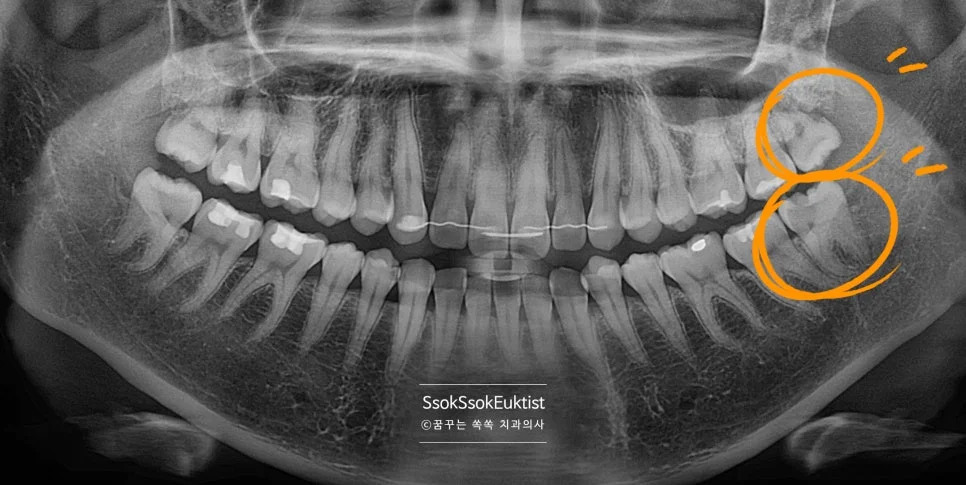

파노라마 엑스레이 — 상악과 하악 사랑니 위치 전체 확인

사랑니 발치, 무조건 해야 할까?

사랑니, 발치해야 할까요?